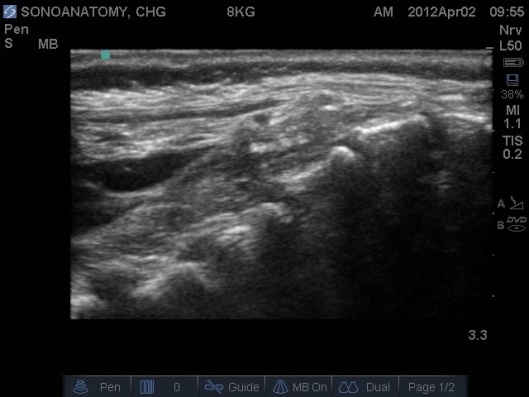

- Position the probe in the midline sagittal plane again, the cannula/needle may be visible. See Fig 8 below.

Fig 8. Ultrasound probe in Midline Longitudinal Plane, needle observed entering caudal space from right top hand corner of screen.

- Inject <0.1ml/kg of normal saline (this avoids wasting valuable LA, and is harmless if injected intravasculalry). See Fig 9 and 10 below. Where the posterior dura can be observed moving anteriorly as the epidural space is expanded.

Fig. 9 Patient in left lateral, cannula in situ with 2 ml syringe of saline attached. Note use of large footprint probe to give greater view of spine and observe for test injection.

Fig 10. Ultrasound probe in Midline Longitudinal position, saline test bolus seen as anechoic area displacing the posterior dura anteriorly.

- Correct cannula position will see the test bolus of saline expand the epidural space, displacing the posterior dura anteriorly.

- If the saline test bolus is not seen then either the cannula/needle is in a vessel or the probe is not positioned correctly (check your probe position).